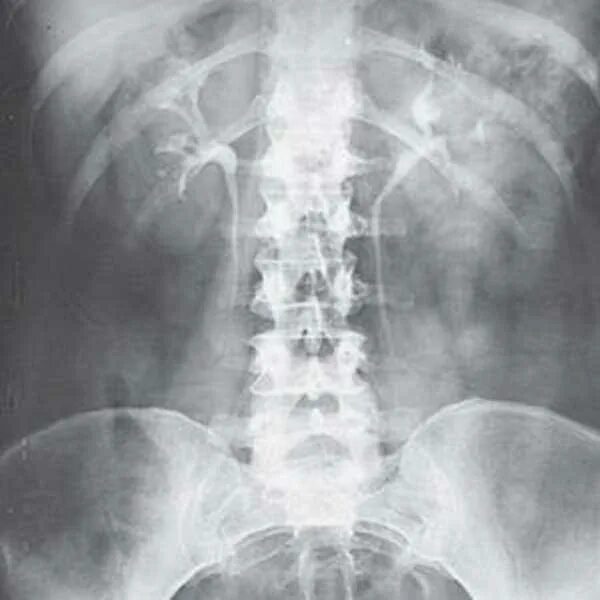

Урография с контрастом